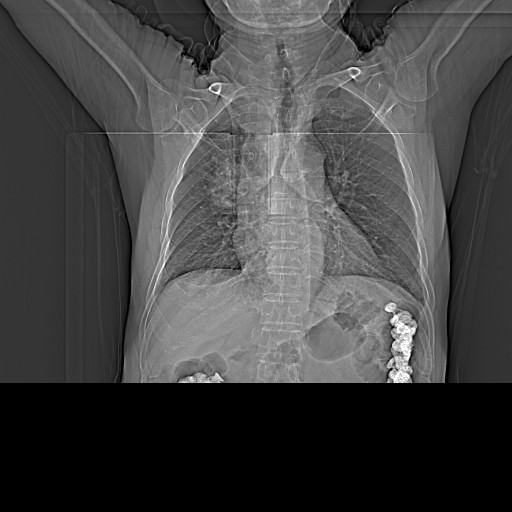

CT50446:胸部会诊

男,76y 胸闷、气短、进食阻噎感2月

右下肺可见团块状斑片状密度增高影,块影内见透光区,纵隔内多发肿大淋巴结,部分融合,食道下段周围见软组织肿块,管腔狭窄,主冠脉钙化,两侧胸膜增厚,考虑右肺癌伴纵隔淋巴结转移,食道受侵?

肺癌伴纵膈淋巴结转移

考虑肺癌并食道及纵隔转移

首先考虑右肺空洞性肺癌伴纵膈淋巴结转移。其次考虑贲门痉挛,在考虑食道癌。

能否考虑双源发肿瘤,食管Ca;肺Ca?

食道下段癌伴肺内及纵隔转移